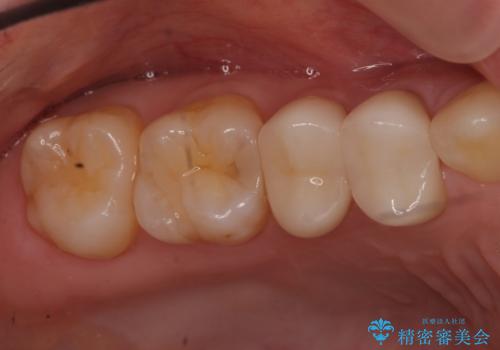

- 約27万円(税別) 右上45 emaxクラウン、仮歯 右上4 精密根管治療、ファイバーコア費用は治療当時の料金となります

なお、根管充填にはMTAを使用しました。

術後は瘻孔、圧痛、打診痛も消失し、根尖病変の縮小もみられました。経過良好です。